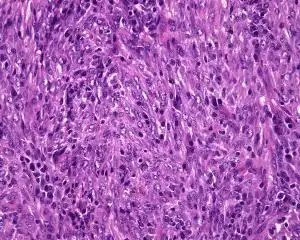

炎性肌纤维母细胞瘤

纤维肉瘤